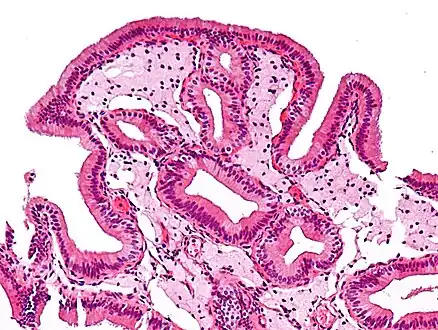

Micrograph of cholesterolosis of the gallbladder

The name strawberry gallbladder comes from the typically stippled appearance of the mucosal surface on gross examination, which resembles a strawberry. Cholesterolosis results from abnormal deposits of cholesterol esters in macrophages within the lamina propria (foam cells) and in mucosal epithelium. The gallbladder may be affected in a patchy localized form or in a diffuse form. The diffuse form macroscopically appears as a bright red mucosa with yellow mottling (due to lipid), hence the term strawberry gallbladder. It is not tied to cholelithiasis (gallstones) or cholecystitis (inflammation of the gallbladder).[2]